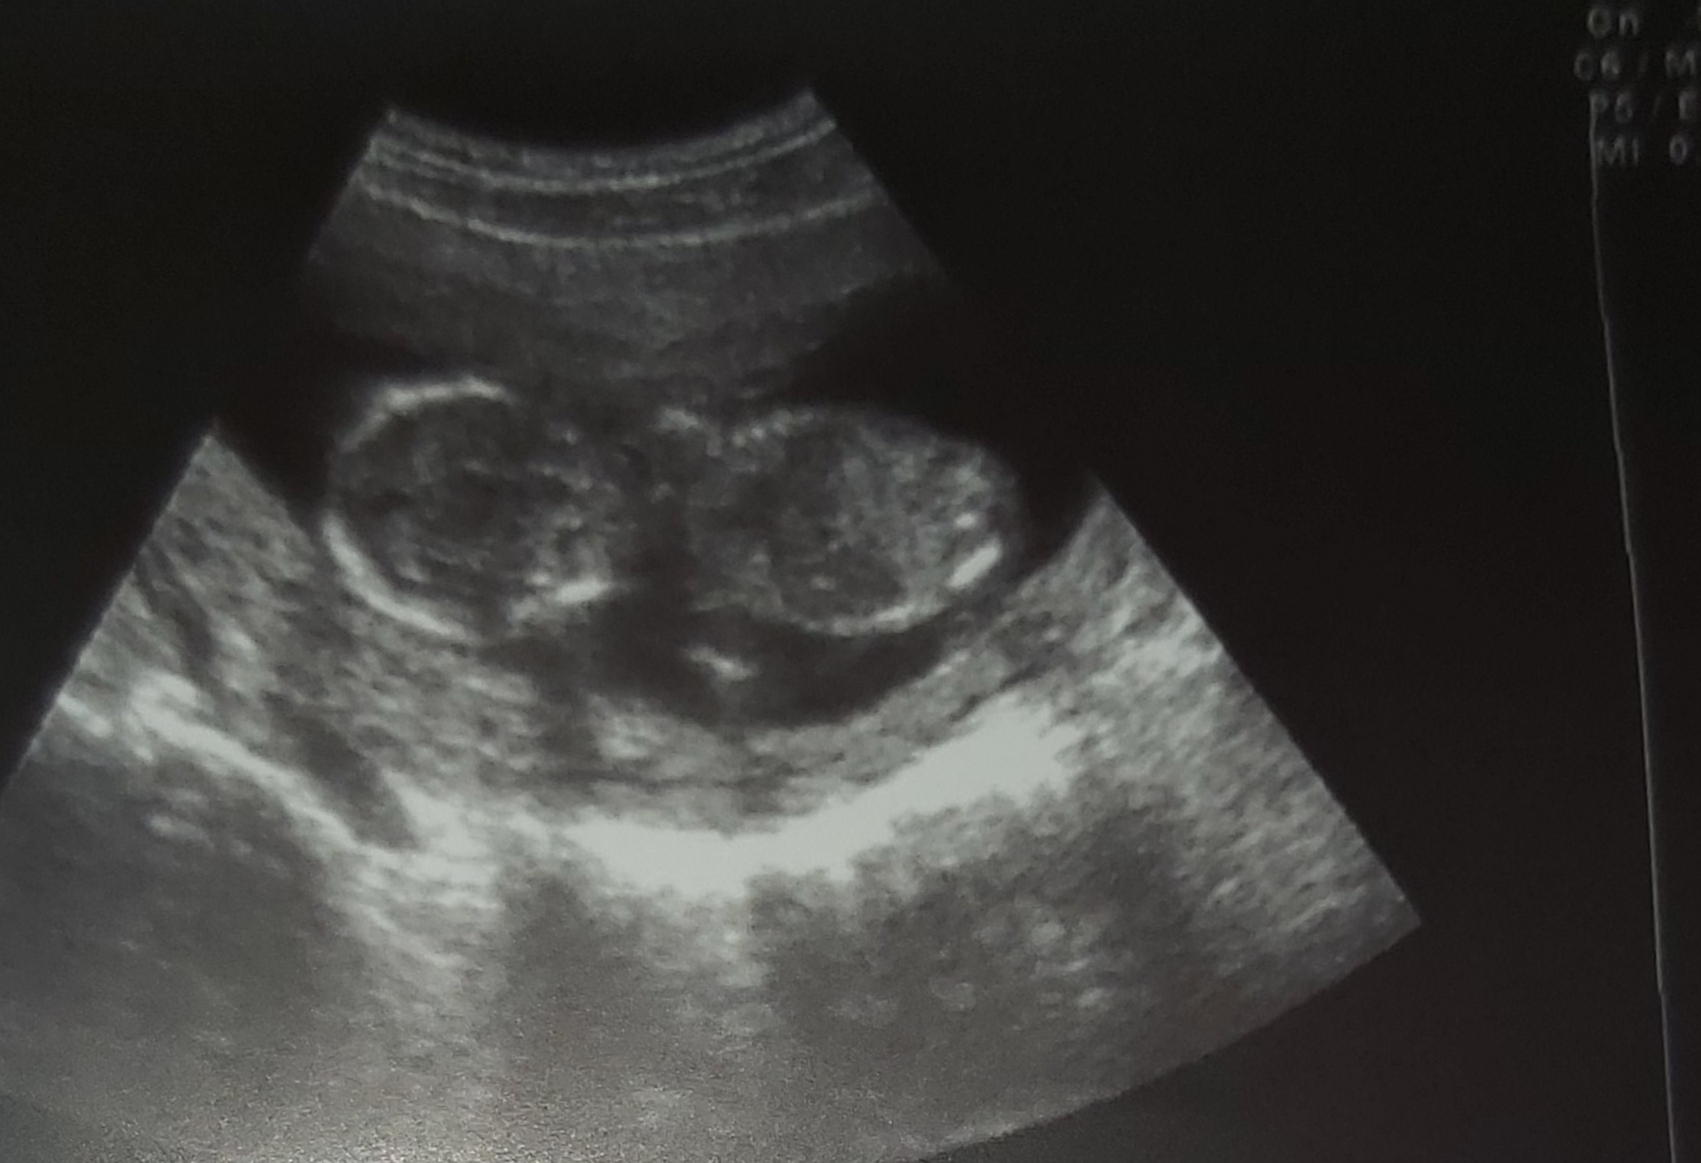

فدات بشم گلم میشه قشنگ دقت کنی ببینی چیه

گلم اون سه تای بالایی برای ۱۲ هفته و ۲ روزمه

این چندتای پایینی برای ۱۴ هفته و ۵ روزمه